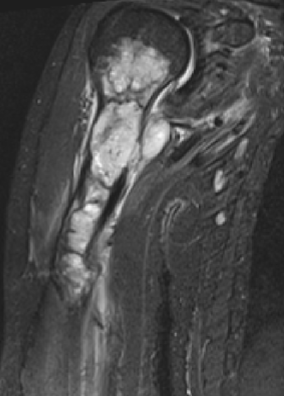

МР-диагностика новообразований конечностей (суставы, кости, мягкие ткани)

- Визуализация патологических изменений в конечностях и суставах

- Оценка и стадирование первичного их поражения, выявление рецидивов

- Дифференциальная диагностика метастазов и других заболеваний костных структур, мягких тканей